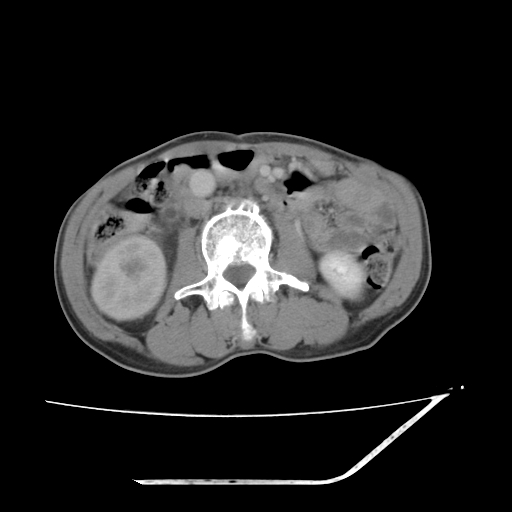

增强

考虑右肾盂癌,肾动脉受侵,右肾功能减退,右肾盂输尿管积水,管壁增厚,考虑种植转移,应该把下面扫完的

考虑右侧肾盂癌。右侧输尿管扩张未扫描完。

右肾盂癌,肾动脉受侵,右肾盂输尿管积水,管壁增厚,考虑种植转移

右肾盂移行细胞癌并右输尿管中段转移.肾积水.

1.右侧肾盂癌伴肾盂积水。

3.右侧上段输尿管扩张,原因:(1)积水所致;(2)种植。